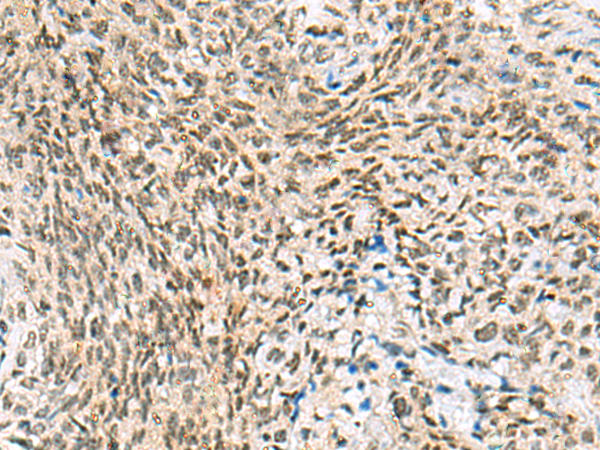

The image is immunohistochemistry of paraffin-embedded Human liver cancer tissue using (C3orf38 Antibody) at dilution 1/95. (Original magnification: ×200)

The image is immunohistochemistry of paraffin-embedded Human cervical cancer tissue using (C3orf38 Antibody) at dilution 1/95. (Original magnification: ×200)